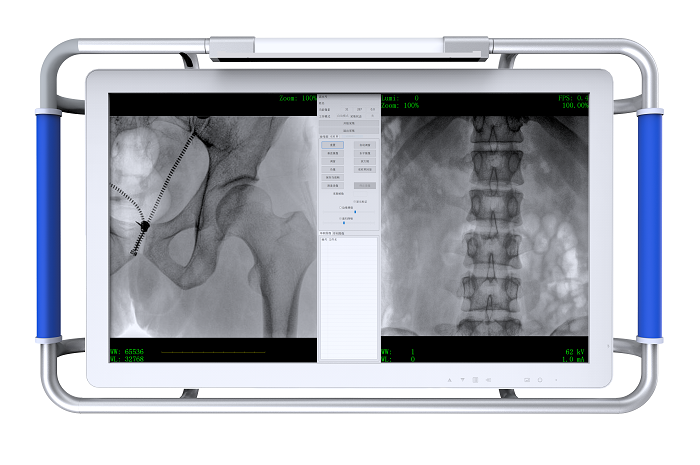

某醫院采購了一臺國產品牌的的C臂機,發現圖像質量會在一兩年后變差,廠家解釋是正常衰減,然后售后工程師調一下就好了。所以為什么有的c臂機的圖像質量會越用越差呢?下面來看看專業人士的分析。

C臂機的圖像質量

國產品牌C臂機